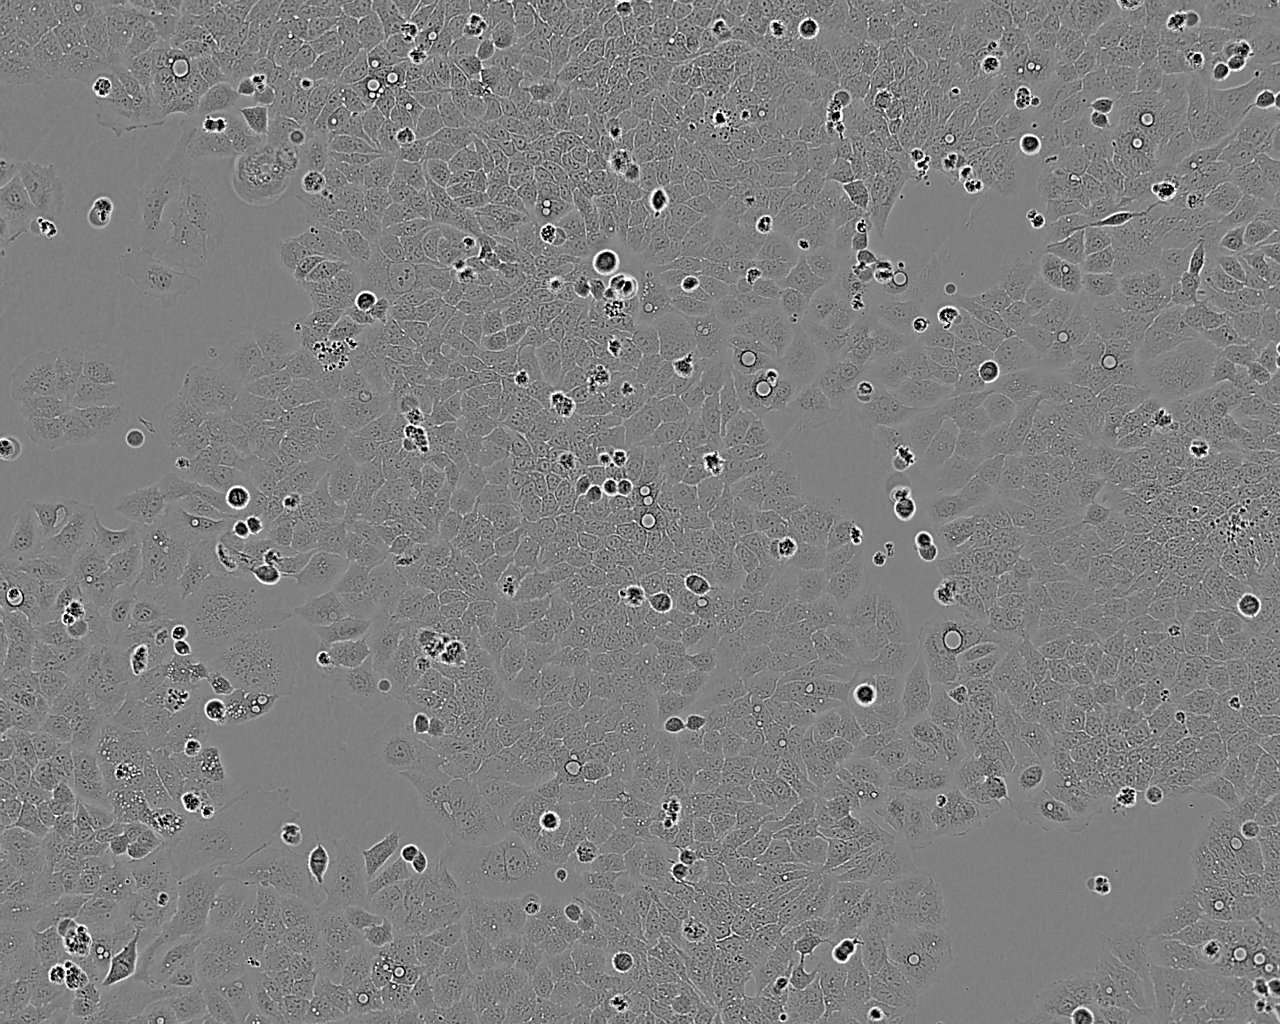

Images